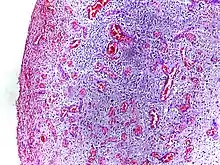

Morphologic patterns

Specific patterns of acute and chronic inflammation are seen during particular situations that arise in the body, such as when inflammation occurs on an epithelial surface, or pyogenic bacteria are involved.

- Fibrinous inflammation: Inflammation resulting in a large increase in vascular permeability allows fibrin to pass through the blood vessels. If an appropriate procoagulative stimulus is present, such as cancer cells,[12] a fibrinous exudate is deposited. This is commonly seen in serous cavities, where the conversion of fibrinous exudate into a scar can occur between serous membranes, limiting their function. The deposit sometimes forms a pseudomembrane sheet. During inflammation of the intestine (pseudomembranous colitis), pseudomembranous tubes can be formed.

- Purulent inflammation: Inflammation resulting in large amount of pus, which consists of neutrophils, dead cells, and fluid. Infection by pyogenic bacteria such as staphylococci is characteristic of this kind of inflammation. Large, localised collections of pus enclosed by surrounding tissues are called abscesses.